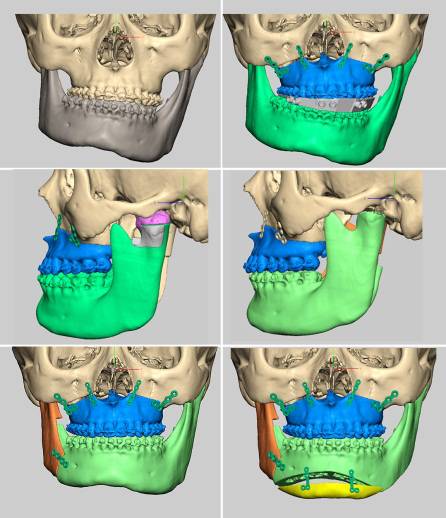

目前可使用软件将螺旋CT或锥束CT等影像学数据经计算机处理后,三维重建患者的颌骨形态,辅助牙颌面畸形的诊断,模拟手术截骨、移动、固定等,并制作相应的数字化导板辅助术中手术实施。同时因为计算机辅助手术设计可以更为直观的观察到术后颌骨的位置,更方便患者直观的了解手术效果,理解手术方案,便于医患沟通交流。

计算机辅助正颌外科手术设计

(摘自“第四章第三节 牙颌面畸形治疗计划”)